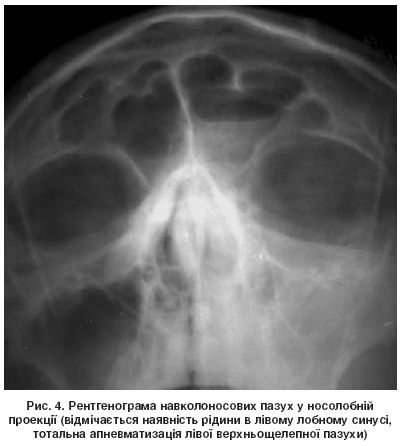

Для оцінювання запальних змін у навколоносових пазухах традиційно використовують рентгенографію в носолобній проекції (рис. 4). Проте звичайна рентгенограма часто не дає змоги одержати точні дані про локалізацію й характер патологічного процесу в синусах і стан внутрішньоносових структур. У разі ускладнень бактеріального синуситу вона не може інформувати про поширення патологічного процесу в порожнину черепа або орбіту, а оцінка стану клітин ґратчастого лабіринту носить орієнтовний характер. Найінформативнішим діагностичним методом є комп’ютерна томографія (КТ), за допомогою якої можна отримати просторове відображення внутрішньоносових структур і навколоносових пазух, а також визначити характер анатомічних порушень, оцінити характер тканин за їх рентгенологічною щільністю (рис. 5). Але найціннішим є те, що комп’ютерні томограми (в аксіальній і коронарній проекціях) є «картою» для планування хірургічного втручання й «путівником» для хірурга під час проведення ендоскопічної ендоназальної операції.